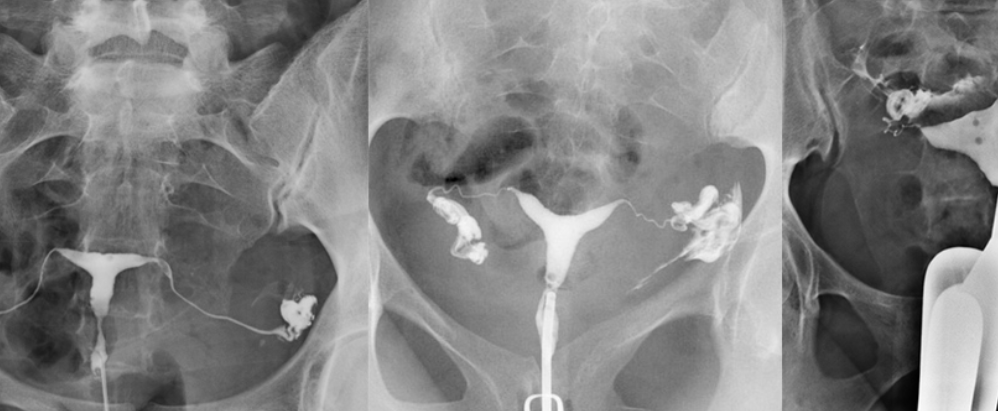

Rahim için çekilen filmlere HSG filmi adı verilir. Bu film çekilerek rahim boşluğunun görüntülenmesi sağlanıyor. Yeni nesil teknolojik cihazlar kullanılarak çekilen filmler, rahimde olan sorunların tespitinde önemli bir rol oynuyor. Aynı zamanda bu sorunların erken tespit edilmesi konusunda fayda sağlıyor. Rahim incelemesi yapılmak istendiğinde bu yönteme başvurulur.

Görüntüleme yöntemi olarak kullanılan HSG, rahim filmi ismiyle hastanelerde yapılıyor. Rahim tüplerinde bir problem varsa bu görüntüleme yöntemi sayesinde tespit edilir. Aynı zamanda gebelik konusunda sorun yaratacak durumların tespiti de sağlanır. Aşılanma ve tüp bebek tedavileri için kullanılan görüntüleme yöntemi de HSG filmleri kapsamında yer alabiliyor.

Rahim filmleri ile rahim boşluğu görüntülenir ve bu bölgede meydana gelmiş sorunlar tespit edilir. Teknolojik cihazlar kullanılarak rahim içerisinin görüntülenmesi işlemine rahim filmi adı verilir. Bu bölgede tıkanma, genişleme ya da daralma gibi birçok problem meydana gelebilir. Rahim filmleri ile bu problemlerin tespit edilmesi ve giderilmesi mümkün oluyor.

Rahim filmleri, rahim ağzı içerisinden verilen bir sıvı aracılığıyla çekilir. Bu sıvı, görüntüleme cihazları tarafından görülür ve rahim içindeki tüpleri inceleme imkânı sunar. Bu sayede de vücuda ya da organlara hiçbir zarar vermeden görüntüleme işlemi yapılır. Makineler, sıvıyı detaylı bir şekilde algılar ve görür. Böylece rahim filminin çekimi gerçekleştirilir.